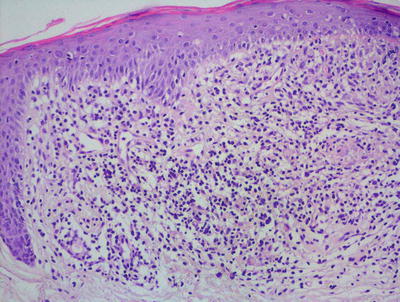

Lichen planus occurring in children has similar histologic features to the same disease in adults. The stratum corneum is hyperkeratotic without acanthosis. The epidermis is acanthotic with hypergranulosis (Fig. 4.2). The rete ridges demonstrate a saw-toothed alteration in appearance. The basal layer is disrupted and in some places obscured by a dense, band-like infiltrate of lymphocytes along the dermal epidermal junction (Fig. 4.3). Dying keratinocytes are present either focally or extensively, resulting in separation of the epidermis from the dermis. In some cases, this may present with clinically apparent bullae (bullous lichen planus) [2]. In older lesions, especially in patients with darker skin tones, post-inflammatory pigment incontinence is detected in the presence of papillary dermal melanophages (lichen planus pigmentosus in its most extensive form). The inflammatory infiltrate consists of lymphocytes and histiocytes. Eosinophils and plasma cells are not common. The infiltrate is restricted to the papillary dermis, and does not ordinarily extend into the reticular dermis [3–5].

Fig. 4.3

In some cases of lichen planus, the epidermis appear papillomatous and hypergranulotic. Scattered dying keratinocytes are seen along with a dense band-like infiltrate and focal exocytosis of lymphocytes into the epidermis